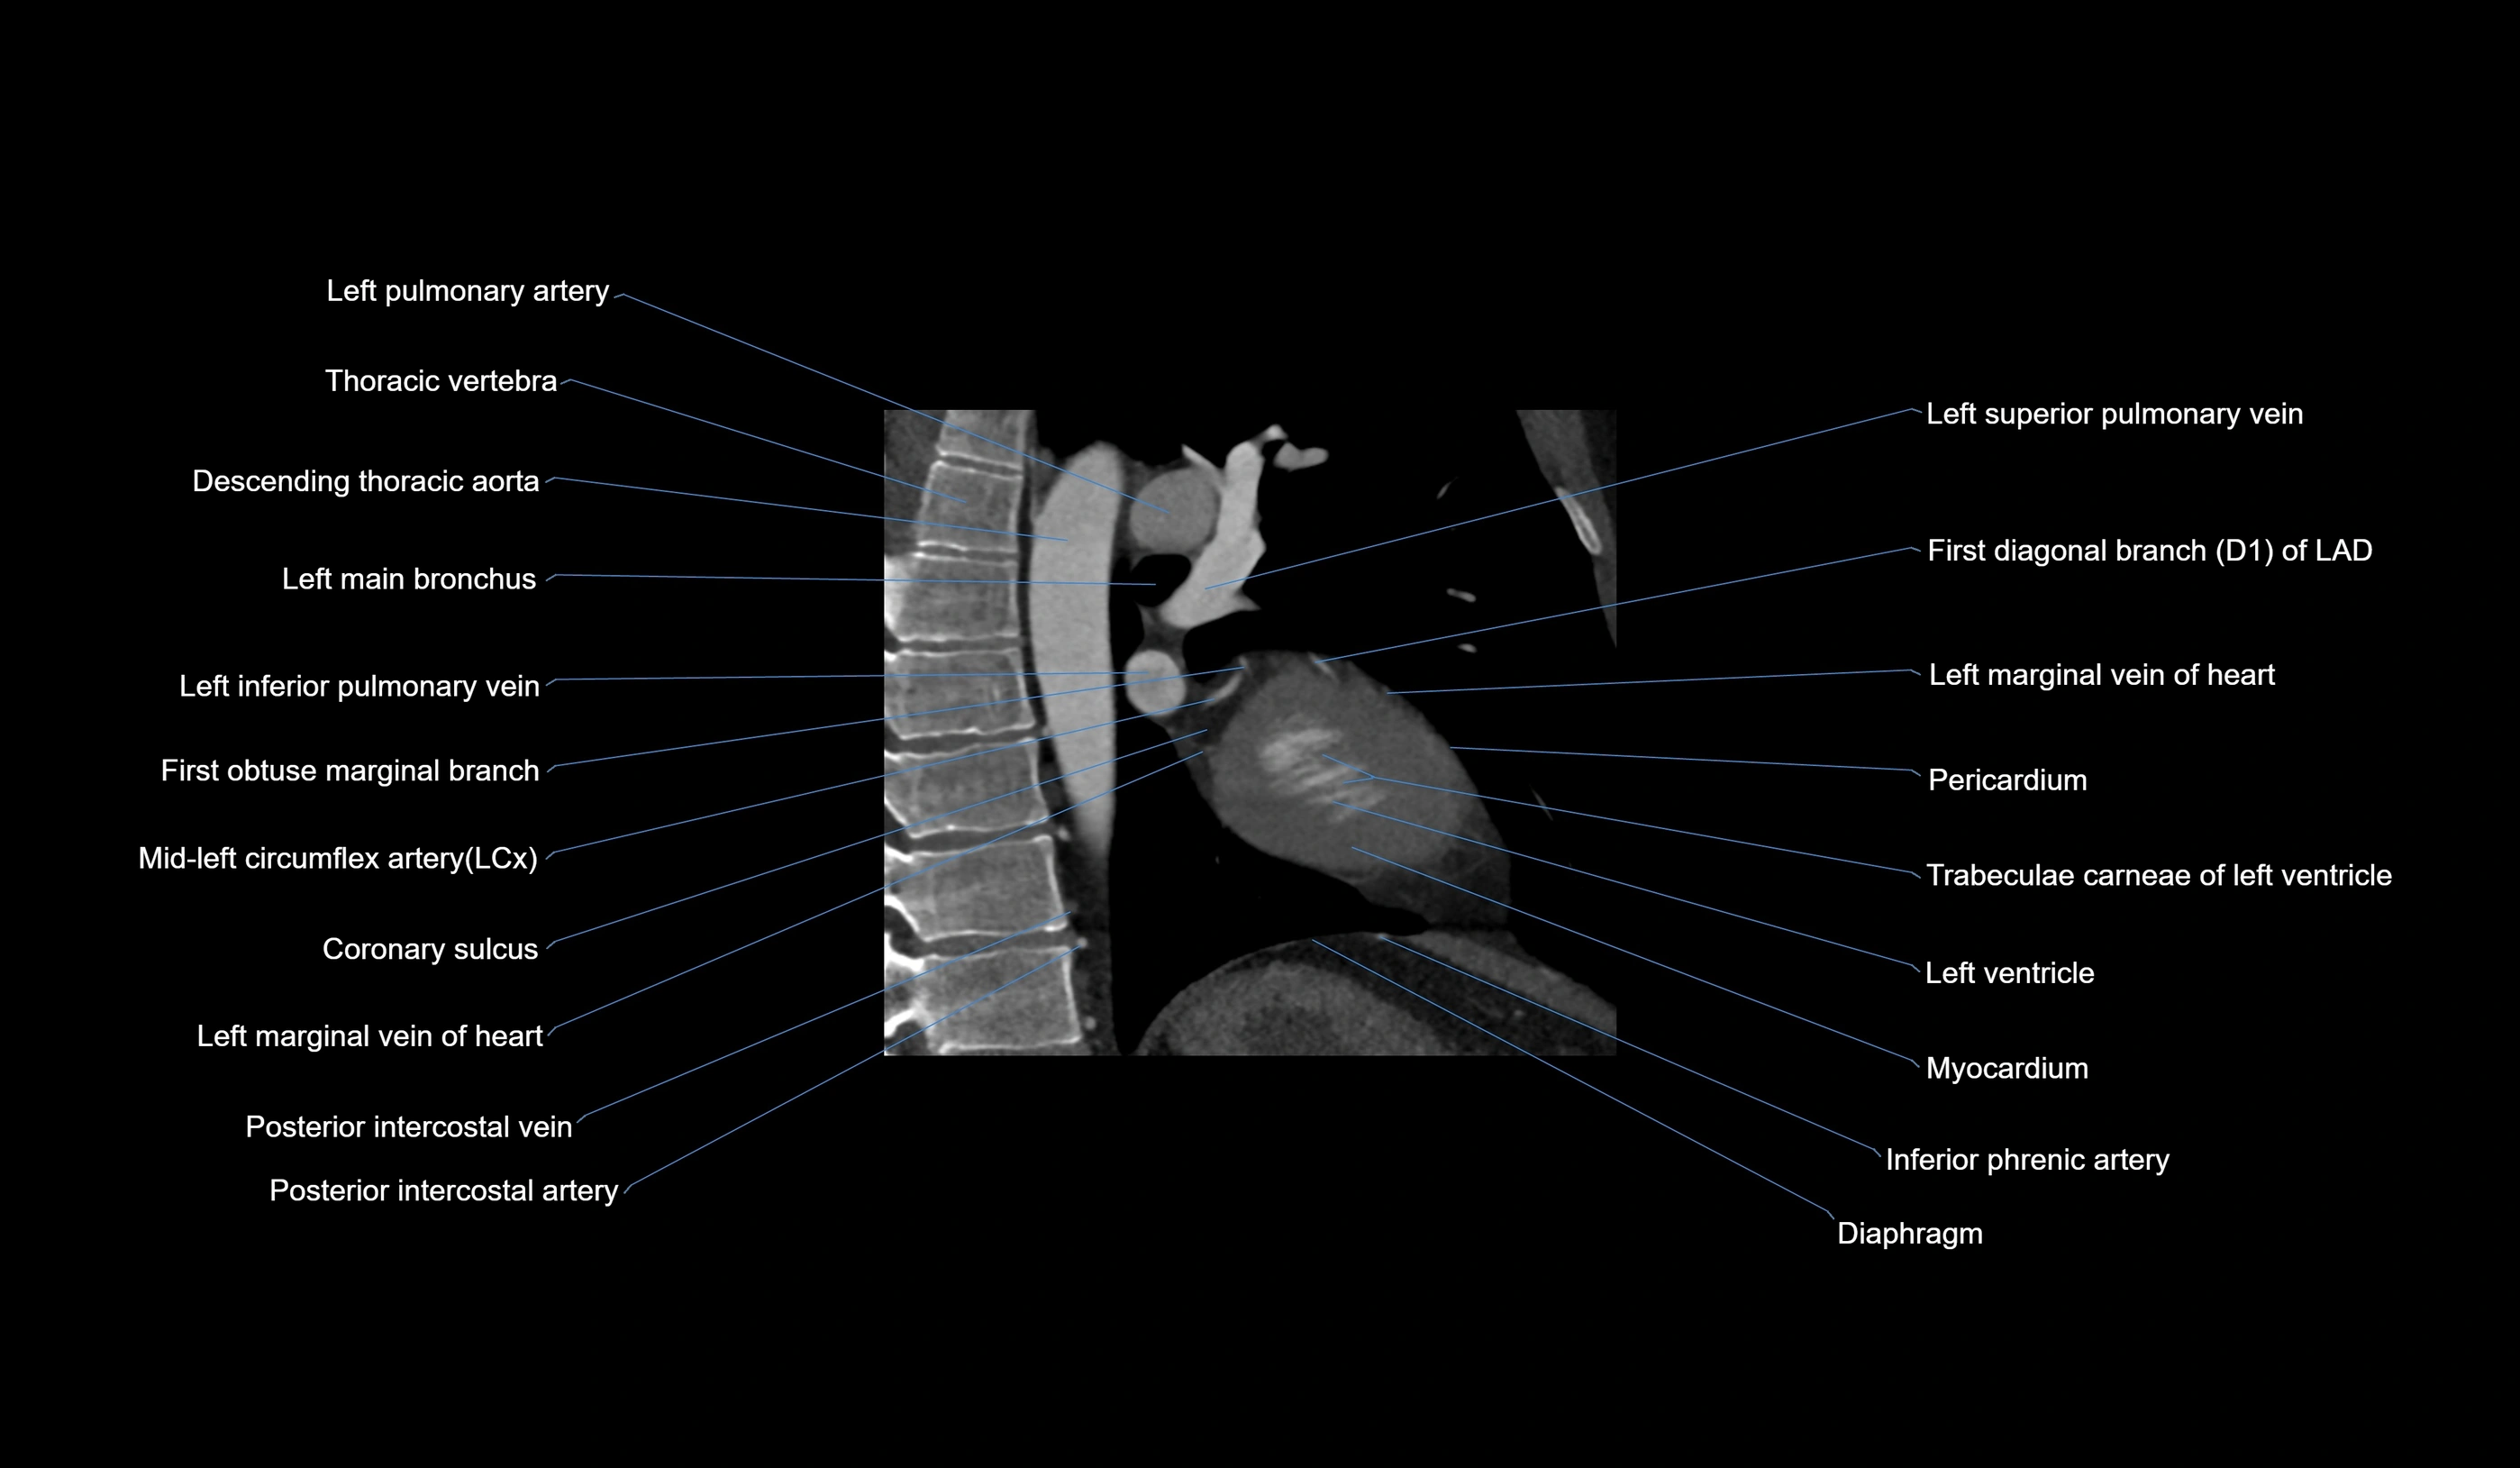

CT images